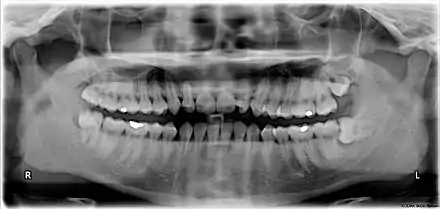

![]() Wisdom teeth in the human mouth for permanent teeth. There are none in deciduous (children's) teeth. | |

The third molar, commonly called wisdom tooth, is the most posterior of the three molars in each quadrant of the human dentition. The age at which wisdom teeth come through (erupt) is variable,[1] but this generally occurs between late teens and early twenties.[2] Most adults have four wisdom teeth, one in each of the four quadrants, but it is possible to have none, fewer, or more, in which case the extras are called supernumerary teeth. Wisdom teeth may become stuck (impacted)[3] against other teeth if there is not enough space for them to come through normally. Impacted wisdom teeth are still sometimes removed for orthodontic treatment, believing that they move the other teeth and cause crowding, though this is not held anymore as true.[4][5]

Wisdom teeth (often notated clinically as M3 for third molar) have long been identified as a source of problems and continue to be the most commonly impacted teeth in the human mouth. Impaction of the wisdom teeth results in a risk of periodontal disease and dental cavities.[24] Impacted wisdom teeth lead to pathology in 12% of cases.[25]